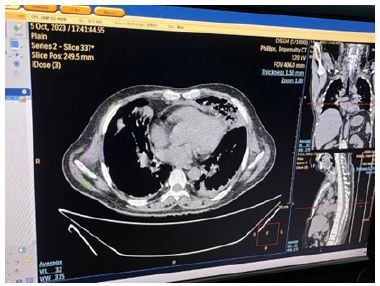

Chest radiograph showed slight widening of mediastinum. Blood for hemoglobin was 11.2gm%; total WBC count was 9.9 X109 /L (Neutrophils 88.1%, Lymphocyte 9.5%, Monocyte 2.4%); platelet count was 36 X109/L; ESR was 40mm per 1sthour; serum creatinine was 4.9mg/dl (0-1.3mg/dl); blood urea was 244.3mg/ dl (10-50mg/dl); serum sodium was 132 ; potassium was 4.4; chloride was 98; total bilirubin was 15.6 mg/dl (0.2-1.0mg/dl); Aspartate aminotransferase was 65U/L (9-48U/L); LDH was 502U/L (200-480U/L). Blood sugar (105.6mg%) and Hb A1 C were normal. Blood for retroviral serology was negative; serology for hepatitis B and C were negative. Computed tomography (CT) neck showed right cervical lymphadenopathy with some areas of break down suggestive of abscess. CT chest revealed features of mediastinitis and mediastinal abscess; they were in continuation with pre-tracheal fascia as seen in CT neck findings (Figures 2-12).

Figure 5: CT chest showing multiple abscess with surrounding opacities in the anterior mediastinum suggestive of mediastinitis and mediastinal abscess, and minimal left pleural effusion.

Figure 6: CT chest showing larger abscess in the anterior mediastinum with minimal left pleural effusion.

Figure 7: CT chest showing larger abscess with surrounding inflammation in the anterior mediastinum with minimal left pleural effusion.

Figure 9: CT chest showing mediastinitis and rounded opacity with air speck at the level of trachea bifurcation.